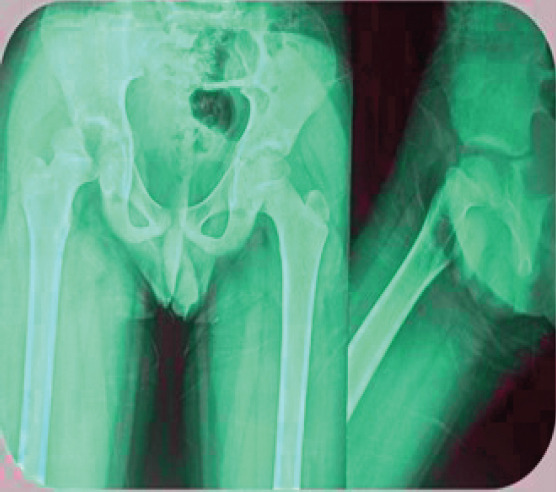

Case report: We present the case report with detailed history, examination, and treatment of a 12-year-old boy with an uncommon site of fracture at right transepiphyseal hip fracture with dislocation. Emergency initial operation was done and followed up for 2-year duration on regular basis. The patient has currently normal gait with painful terminally restricted movements.